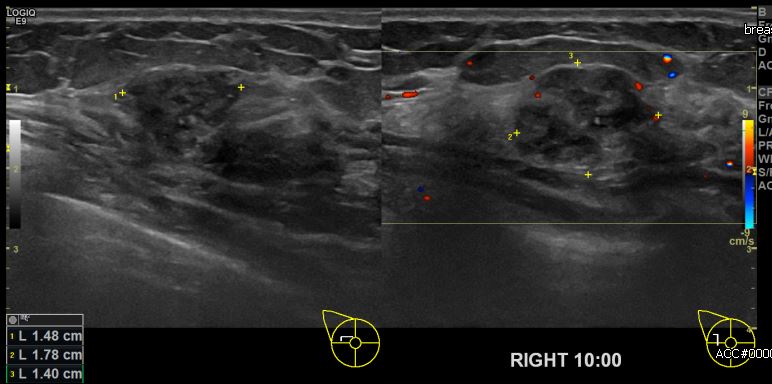

상기환자 건장검진상 이상소견으로 내원하신 50대 여성분으로 우측 10시 방향에

의심스러운 멍울 조직검사 시행하여 우측 유관암 진단 되었습니다.